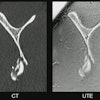

A 47-year-old female patient with chronic pain in the left lower back/buttock with unknown cause. PET demonstrated focally increased FDG uptake at the left facet L3-4 l. MRI shows minimal fluid, but no edema. Follow-up PET-MRI after six months shows a similar pattern. The patient is on the waiting list for targeted facet joint infiltration (typically not covered by insurance in the Netherlands).Image courtesy of Marijn Mostert